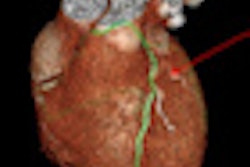

The study sought to assess the impact of patient population characteristics on accuracy by CTA to detect obstructive coronary artery disease (CAD). The analysis was based on data from the CORE 64 trial, a prospective, multicenter study performed at nine hospitals in seven countries. It was designed to evaluate CCTA's diagnostic accuracy in patients with suspected or known significant disease.

The CORE 64 investigators evaluated 371 patients using both CCTA and cardiac catheterization for detecting obstructive CAD, defined as 50% or greater luminal stenosis by quantitative coronary angiography.

Each underwent two CT scans (coronary calcium scoring and CCTA ) using 64-detector-row scanners with a slice thickness of 0.5 mm (Aquilion 64, Toshiba America Medical Systems) within 30 days of undergoing conventional coronary angiography.